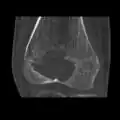

Other imaging techniques involve computed tomography (CT), magnetic resonance imaging (MRI), and bone scans, which may be helpful in determining the anatomical boundaries, associated edema, or biological activity of the chondroblastoma, respectively.[8][10] MRI studies may show extensive oedema around the lesion and show variable T2 signal intensity.[15]

1. c. CT scan of chondroblastoma of thigh bone near knee (cross-section view)